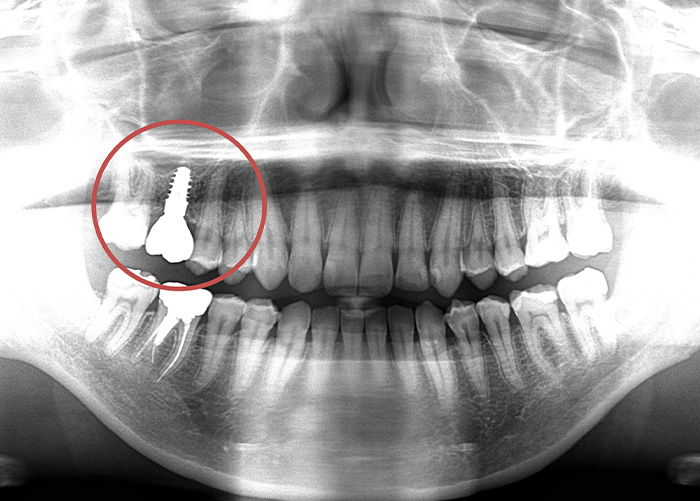

Case.05

![]() |

|---|

| 主訴 | 右上の奥歯が歯がないので入れたい |

|---|---|

| 治療期間 | 6ヵ月 |

| 治療費 | 390,000円(税込429,000円)(インプラントリーズナブルプラン1歯) |

| 治療内容 | 右上の奥歯にインプラントを入れて、被せ物(ジルコニアシンプル)を被せます。 |

| 治療のリスク | インプラントは歯周病になる可能性があります。 一定の割合で生着しないで再埋入が必要になる場合があります。 |